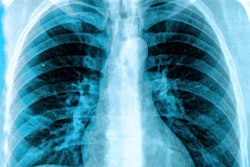

The researchers also noted that the algorithm generates gradient-weighted class-activation maps (Grad-CAM) to localize the anatomic regions that contributed to its age estimate.

Gradient-weighted class activation maps can localize anatomy contributing to CXR-Age estimates. In this 55-year old man, the CXR-Age model focuses on the aortic knob. Image courtesy of Vineet Raghu, PhD, and Dr. Michael Lu.These maps show that CXR-Age commonly focuses on the mediastinum, the cardiac silhouette, and the aortic knob -- anatomy that dilates and becomes tortuous with aging.

"Activations were also seen over other anatomy, including the diaphragmatic silhouette, the upper mediastinum, and the low neck," the authors wrote.